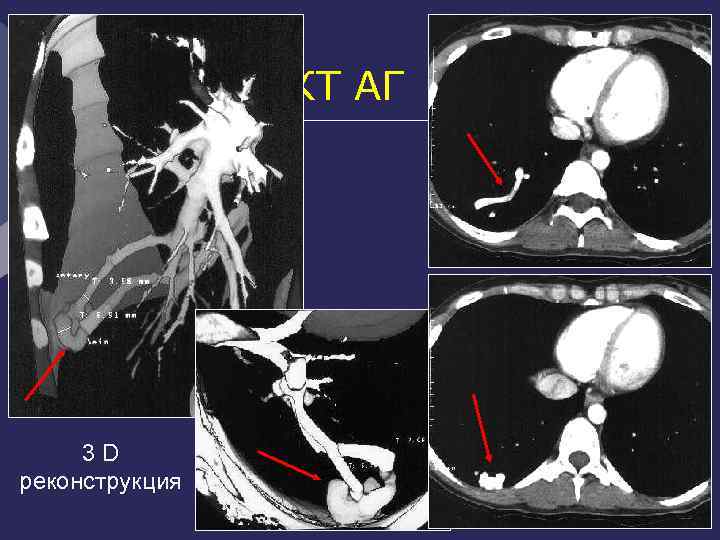

Аномальный сосуд, отходящий от аорты ЧС ВБА КТ-АГ. 3 D объемная МР-АГ реконструкция

Легочная секвестрация Аномальный сосуд, отходящий от Ао выше диафрагмы

КТ АГ 3 D реконструкция